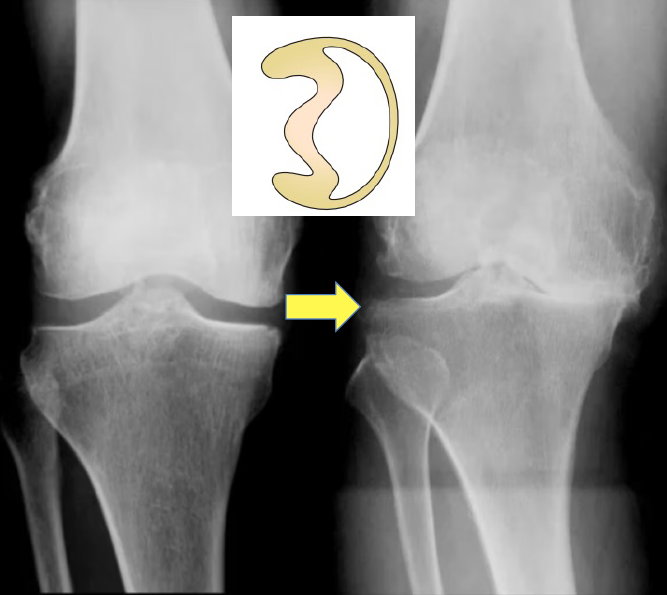

膝の怪我において、前十字靭帯(ACL)と並んで「要(かなめ)」となるのが半月板です。かつては傷ついた半月板を切り取ることが一般的でしたが、現在は「可能な限り残す」ことが世界のスタンダードとなっています。

半月板は膝の関節の間にある三日月型の軟骨組織で、内側と外側に一つずつあります。これらは単なるクッションではなく、膝がスムーズに動くために不可欠な役割を担っています。

なぜ「切る」のではなく「縫う(温存)」のか?

半月板が損傷した際、傷んだ部分を切り取れば、一時的に痛みは消えるかもしれません。しかし、そこには将来的な大きな代償が伴います。

半月板を失った膝の末路

半月板が正常に機能しなくなると、膝は次のように段階的に壊れていくことがわかっています。

- 半月板損傷・切除: クッション機能が失われる。

- 軟骨の摩耗: 骨同士が直接ぶつかり、軟骨がすり減る。

- 変形性膝関節症へ: 膝が変形し、激しい痛みで歩行が困難になる。